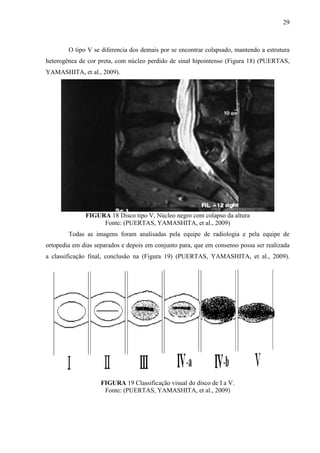

O tipo V se diferencia dos demais por se encontrar colapsado, mantendo a estrutura

heterogênea de cor preta, com núcleo perdido de sinal hipointenso (Figura 18) (PUERTAS,

YAMASHITA, et al., 2009).

FIGURA 18 Disco tipo V, Núcleo negro com colapso da altura

Fonte: (PUERTAS, YAMASHITA, et al., 2009)

Todas as imagens foram analisadas pela equipe de radiologia e pela equipe de

ortopedia em dias separados e depois em conjunto para, que em consenso possa ser realizada

a classificação final, conclusão na (Figura 19) (PUERTAS, YAMASHITA, et al., 2009).

FIGURA 19 Classificação visual do disco de I a V.